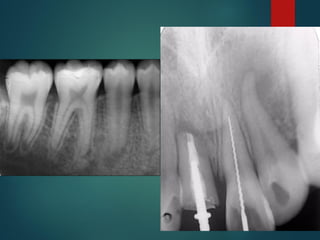

Diagnostico Radiografico de Caries

 Alrededor del 30% de las caries existentes no

pueden verse sin control radiográfico

 Las radiografías de aleta de mordida son las más

adecuadas para descubrir estados precoces de

la caries

La caries es detectable

radiográficamente por que

produce una desmineralización del

diente, esta zona permite un paso

mayor de Rayos X que impresionan

la película